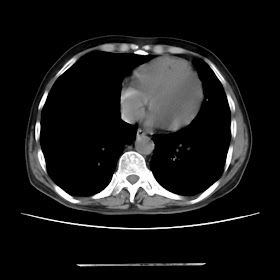

A 54 years old man with intermittent cough with expectoration and shortness of breath since childhood (Radiology)

Radiological images: